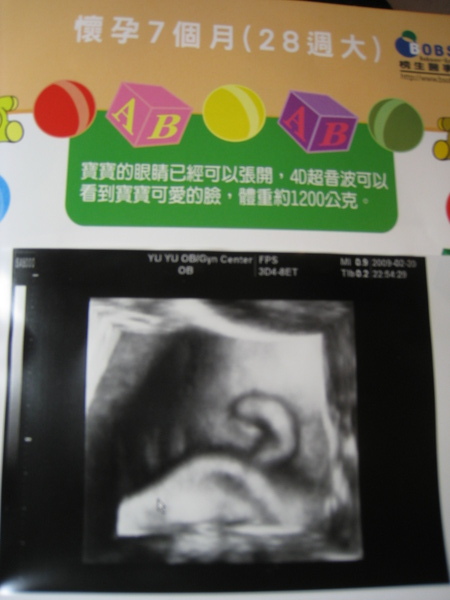

還有...這一次小柚子的臉埋的太深了...

超音波只能照到一隻耳朵..

太妙了啦超音波的圖上就是一隻耳朵耶....笑死我了..

身高:約30cm

體重:約1700g

頭圍:大了一週..